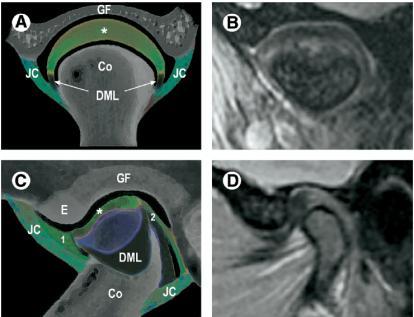

Figure 1 Schematic (A, C) and magnetic resonance T2*-weighted (B, D) images of the temporomandibular joint (TMJ),

in the coronal (A, B) and sagittal (C, D) view. Two osseous elements form the TMJ: the squamous portion of the

temporal bone (GF and E) and the condylar head of the mandible (Co). An articular capsule (JC) attaches to the condyle

and temporal bone. In the closed-mouth position, the condyle (Co) is housed in the bony roof of the glenoid fossa (GF).

The articular eminence (E) forms the anterior wall of the glenoid fossa and represents the load-bearing portion of the

joint during function. The entire articular surface of the temporal bone (GF and E) is saddle shaped with a variable

degree of convexity and concavity. The condylar head may also have a significant variation in size and form, with a

rounded to flattened superior surface. An articular disc (*) is interposed between the articular surfaces of the TMJ. In

the coronal view (A, B), the inferior, concave surface of the disc matches the articular surface of the condylar head. The

superior surface of the disc is slightly convex, fitting the concave surface of the articular fossa. The articular disc is firmly

attached to the medial and lateral poles of the condyle by the collateral, disco-mandibular ligaments (DML). These

attachments increase the medial-lateral stability of the disc during condylar movements. Similarly, connective fibers

inserted between the anterior and posterior margins of the disc and the capsule (1, 2) participate actively in stabilizing

the disc-condyle complex during function. (Color version of figure is available online.)

TMJ diarthrodial joint temporal bone squamous portion mandible condyle로 구성. 이 두개는 fibrous capsule로 둘러싸여 있고 disc articulation .

disc joint capsule condyle lateral margin에 고정.

synovial membrane articulating surface를 제외한 capsule disc inner side를 덮고 있음. synovial fluid는 이membrane에서 생성되며 joint를 채우고 있다.